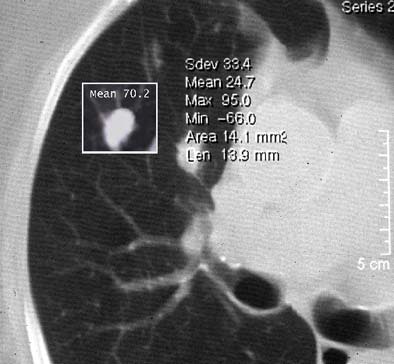

![]() |

| Volumetric analysis of nodule size shows a doubling rate of greater than 750 days. |